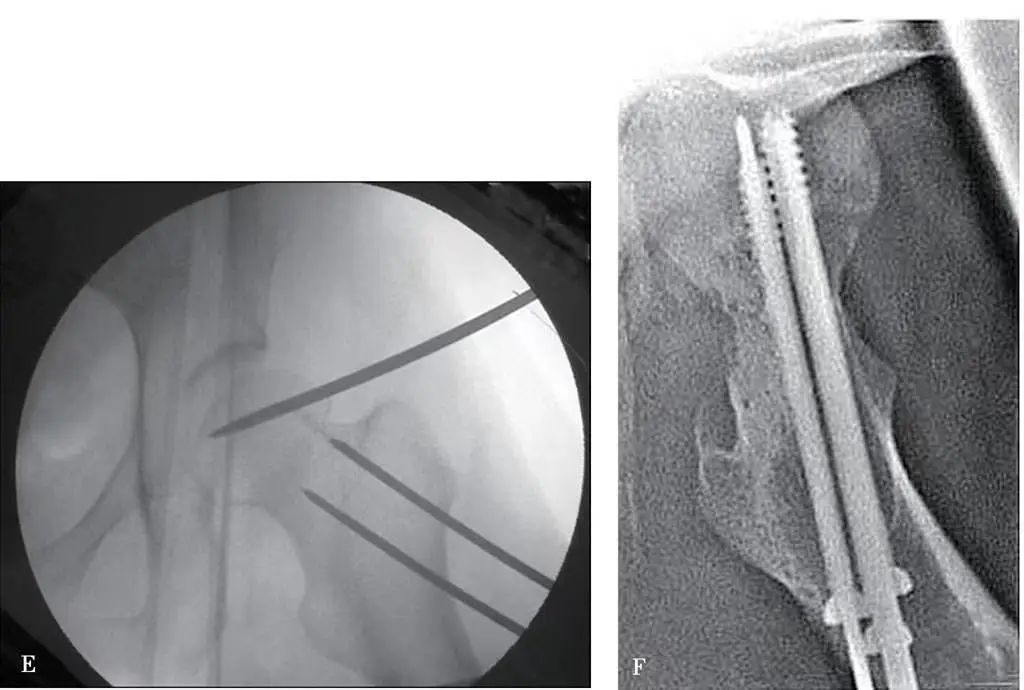

3,0 ila 3,5 mm çaplı dairesel bir kemik iğnesi, kasık bağı ile femoral arterin birleşiminin 1 ila 2 cm altından femur başının ön kısmına dikey olarak deriden geçirilir ve iğne, C kollu makinenin gözetiminde femur başının merkezine doğru daha derine döndürülür (Şekil 1B).

Meraklı kuvveti güçlendirmek için, iğnenin ucu derinin dışında kalacak şekilde, bu iğneye 4-5 mm paralel ikinci bir kemik dairesel iğne yerleştirilebilir.

Büyük trokanter içinden, servikal sapın açısına ve öne eğim açısına uygun olarak perkütan olarak 3,5 mm çapında iki adet dairesel kemik iğnesi delinerek femur boynu kırığının distal ucuna ulaşılır (kırığın içinden geçmeyin) ve iğnenin ucu cilt dışında bırakılır.

Operatör iki takım iğne kuyruğunu iki eliyle tutar ve asistanın işbirliğiyle baş ve boyun kırık bölümlerini birbiriyle hizalanacak şekilde ayarlar (Şekil 1C-E).

Hizalama tatmin edici olduktan sonra, büyük trokantere yerleştirilen yuvarlak kemik pimi, geçici sabitleme için femur başına vidalanır ve daha sonra femur başına birkaç içi boş vida yerleştirilir (Şekil 1F).

Şekil 1 Perkütan iğne yardımıyla yeniden konumlandırılan femur boynu kırığı